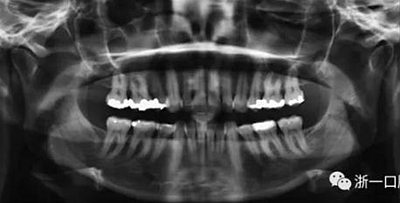

患者曾行正畸治療,現覺笑容不美觀前來就診?;颊哒嬗^及側貌示下頜發(fā)育不足,偏高角,唇閉合不全。上下頜中線齊。覆合、覆蓋4毫米。磨牙關系及尖牙關系II類。上頜擁擠度4mm,下頜擁擠度6mm。4顆第一前磨牙在第一次正畸治療時已拔除。上下牙弓呈尖圓型,牙弓狹窄。

頭影測量分析,SNA角84°,ANB角6°,高角型,詳見下表。

全麻下進行上頜骨腭中縫骨皮質劈開及下頜正中劈開術。手術后,用X光片檢查上頜骨和下頜骨中線切口的位置和方向。

術后第9天開始旋轉擴弓器,每天轉2次,每次轉90度,即擴開0.5mm。每隔1周進行檢查,目標上頜擴開9mm,下頜擴開6mm。18天后,上頜中切牙間出現8mm間隙。下頜出現6mm間隙,(于13天出現后,停止旋轉擴弓器)。在擴弓器旋轉3天后,拍片發(fā)現左下頜中切牙遠中牙根中段有一條低密度陰影,臨床冷熱診反應遲鈍,可能為術中損傷所致。牙體牙髓科會診,建議行根管治療,故行根管治療。